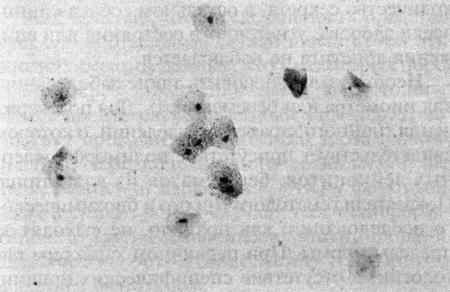

Повышение концентрации эстрадиола в период проэструса стимулирует деление клеток в базальных слоях вагинального эпителия, но затем концентрация эстрадиола, а соответственно и эндокринная поддержка образования нового, многослойного эпителия снижается, поэтому в образце обнаруживается больше мертвых ороговевших клеток. По мере развития проэструса снижается количество эпителиальных клеток, содержащих ядро. С начала до середины проэструса в вагинальных мазках обнаруживают повышенное содержание эритроцитов. Пик ороговения совпадает с началом повышения концентрации прогестерона; однако в начале эструса исследование не обнаруживает характерных особенностей, которые могли бы указывать на начало фертильного периода. Как правило, такой период наступает несколькими днями позже (табл. 1.1). Тем не менее вагинальная цитология остается популярным методом определения репродуктивного статуса суки из-за своей дешевизны, простоты и доступности. Для получения образца используют ватный тампон, предпочтительно небольшой, который вводят во влагалище и осторожно берут мазок. Полученные клетки помещают под микроскоп, а затем окрашивают контрастным (трихромом) или неконтрастным (например, препаратом Diff-Quik) веществом. При таком окрашивании мертвые кератинизированные клетки становятся оранжевыми, тогда как активные ядерные клетки, а также базальные и парабазальные эпителиальные клетки приобретают различные оттенки от голубого до зеленого.

Фиг. 2.2.

Вагинальные выделения кошки (а). Выделения, типичные для фазы эструса. Большая часть клеток представляет собой безъядерные кератинизированные клетки или клетки с пикнотическим ядром. Присутствуют промежуточные клетки (b). Выделения, характерные для метэструса, — «течки», иногда наблюдаемой у кошек в конце эструса. Присутствуют поверхностные и промежуточные клетки, повышено содержание лейкоцитов. Этот короткий метэструс наблюдается в течение 24–48 часов (см. Приложение)